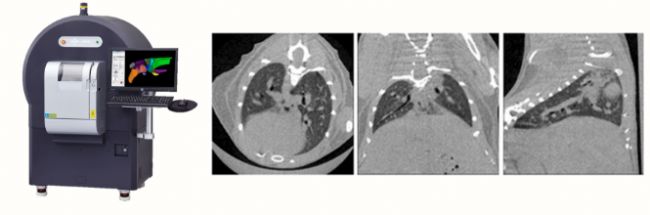

通過上述的介紹,我們不難發(fā)現(xiàn),基于microCT可以快速對全肺和局部的肺組織進(jìn)行各項(xiàng)功能性參數(shù)的測量。借助機(jī)械呼吸機(jī)和胸內(nèi)壓的測量,還可以無創(chuàng)地得到肺的順應(yīng)性和氣道阻力等衍生參數(shù),從而全面的對肺功能進(jìn)行完整評估,揭示肺部疾病病理變化的組織不均一性。珀金埃爾默的QuantumGX2快速活體microCT利用高幀數(shù)高靈敏度的CMOS平板探測器能夠兼顧時(shí)間與信噪比,可在活體水平對模型進(jìn)行連續(xù)時(shí)間點(diǎn)的長時(shí)間觀測,是評估肺部病理生理變化經(jīng)濟(jì)且高效的工具。